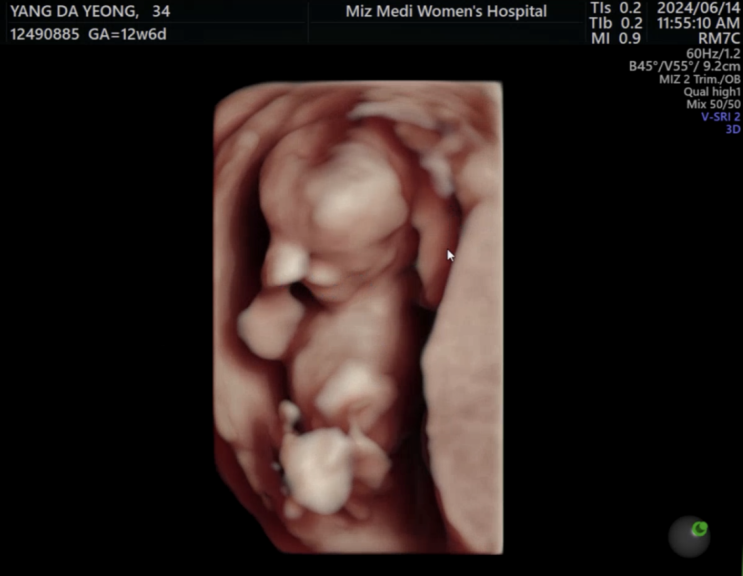

12주

입체초음파 흑백 초음파 아기만 보다가 처음으로 인간모양인 입체 아기를 보게되었다!!! 아랫배가 슬슬 땡...